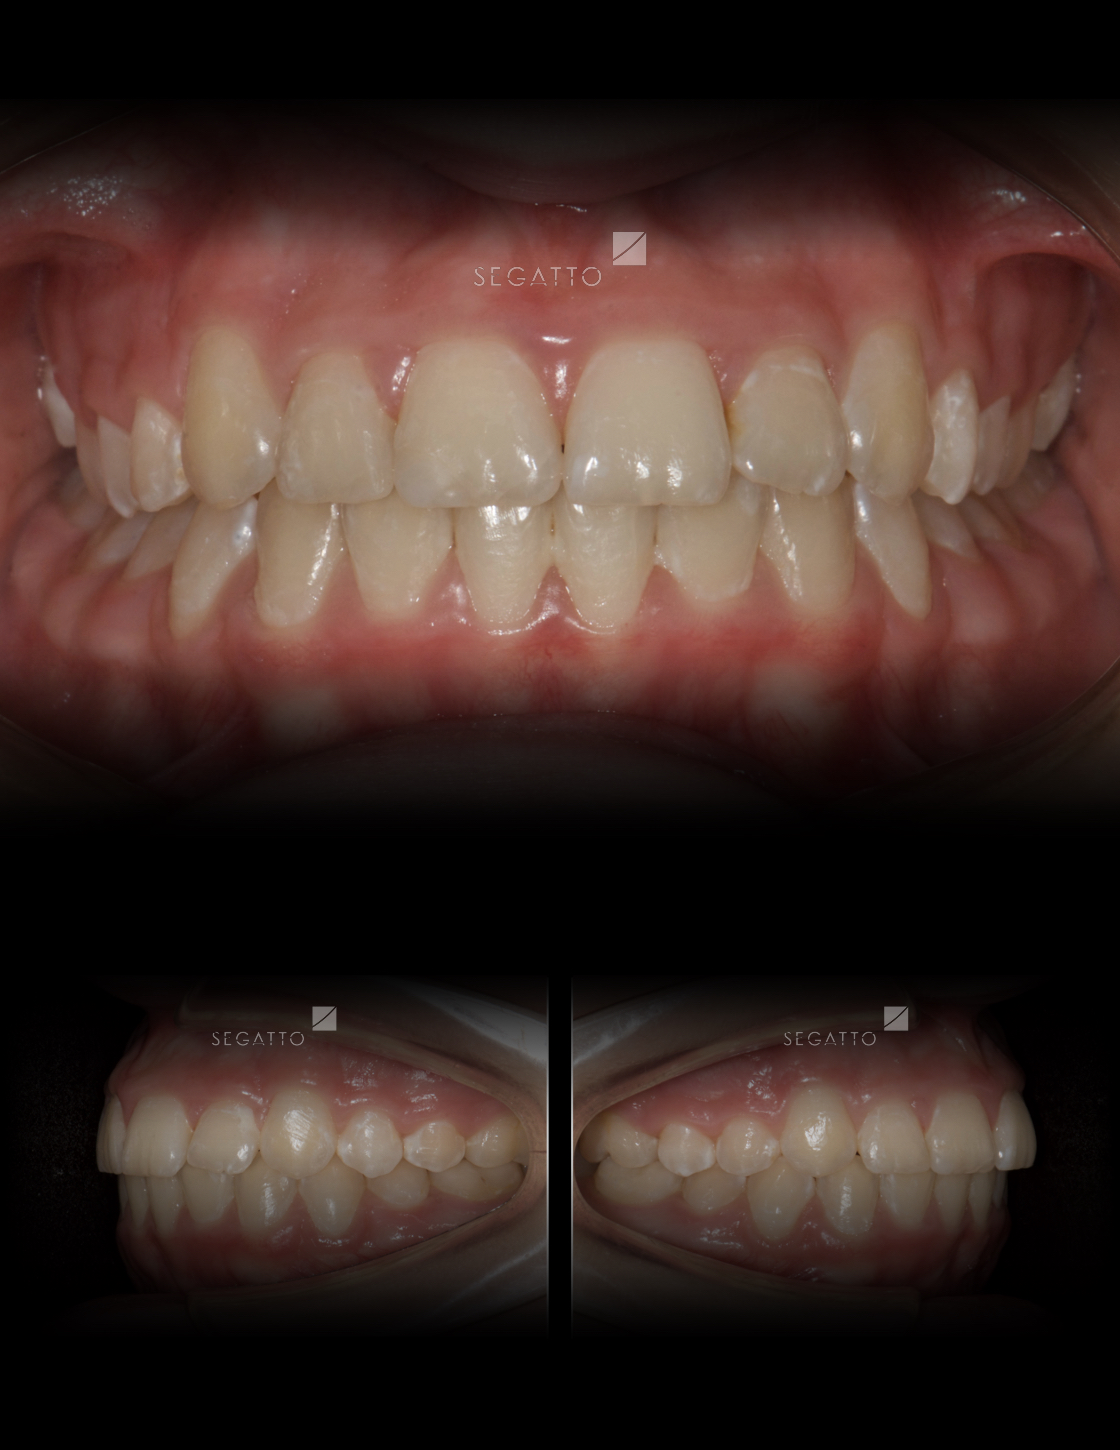

Orthodontics

Cases